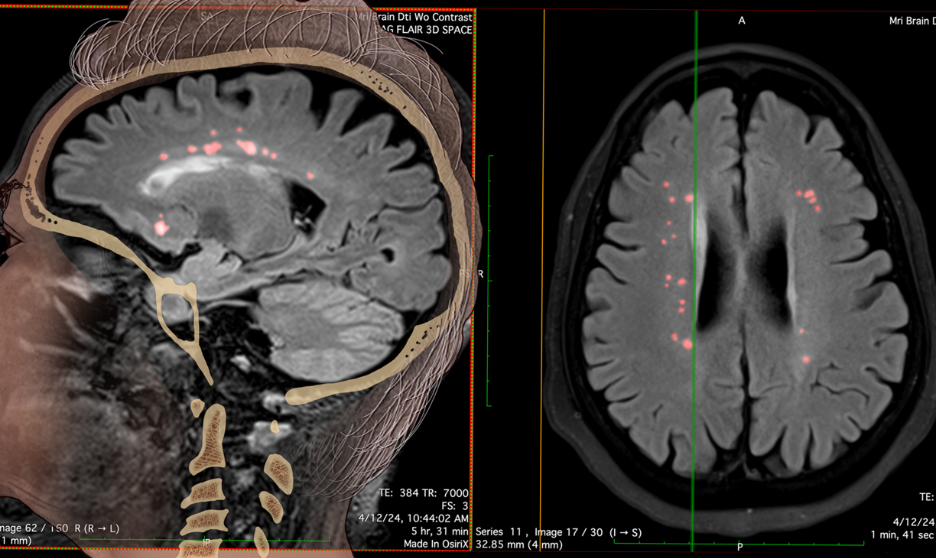

- Advanced brain scans (DTI/MRI) showed changes that happen after a head injury.

- Imaging tests revealed a small loss of brain tissue in the memory area, which explained why she was having trouble remembering things.

All of this clear, scientific evidence helped Crosley Law prove that Audrey’s brain injury happened at the time of the crash and not months later, as the defense tried to argue.